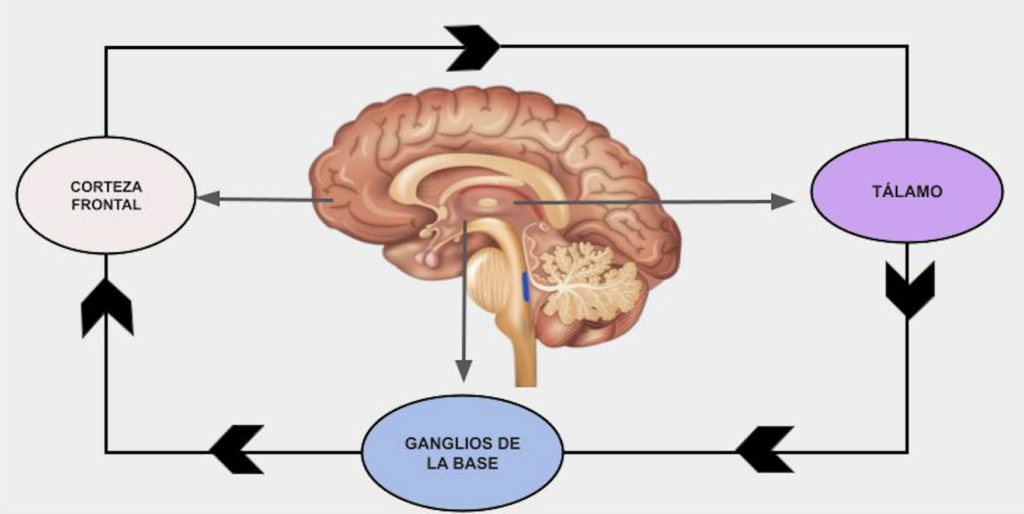

EDUCACIÓN MÉDICA CONTINUA. Trastorno por excoriación cutánea: fisiopatológica y tratamiento

Benítez MS y col.

El trastorno por excoriación cutánea se caracteriza por el rascado repetitivo y compulsivo de la piel, lo cual produce daño tisular. Afecta más frecuentemente a mujeres y su inicio suele coincidir con la pubertad, favorecido por cambios corporales, emocionales y dermatosis como el acné. Las zonas más afectadas son la cara, los brazos y las manos (áreas de fácil acceso), con predominio del lado no dominante. Estos comportamientos se consideran adicciones conductuales ya que presentan un deseo previo a la conducta, placer durante su realización, y una repetición compulsiva y persistente del comportamiento.

Los circuitos neuronales que conectan la corteza cerebral con los ganglios basales, denominados circuitos cortico-estriatales-tálamo-corticales, desempeñan un papel clave en la formación de hábitos.

En un número considerable de casos, la consulta dermatológica constituye con frecuencia el primer punto de contacto médico de estos pacientes. Una escucha atenta y empática resulta fundamental para establecer una adecuada relación médico-paciente, facilitando el abordaje integral del caso.

La terapia cognitivo conductual busca la readaptación del paciente en los planos físico, emocional y conductual; se destaca la terapia de reversión de hábitos, que tiene como objetivo reemplazar las conductas compulsivas por otras alternativas más adaptativas.

Las guías clínicas recomiendan el uso de fármacos que actúan sobre las vías serotoninérgicas como los inhibidores selectivos de la recaptación de serotonina. Aproximadamente el 30% de los pacientes no responde, por lo que una alternativa terapéutica son los fármacos moduladores del sistema glutamatérgico: N-acetilcisteína (dosis de 1200 a 2400 mg/día) y memantina (dosis de 10 a 20 mg/día).

Circuito cortico-estriado-tálamo-cortical: hábitos, movimientos y recompensa